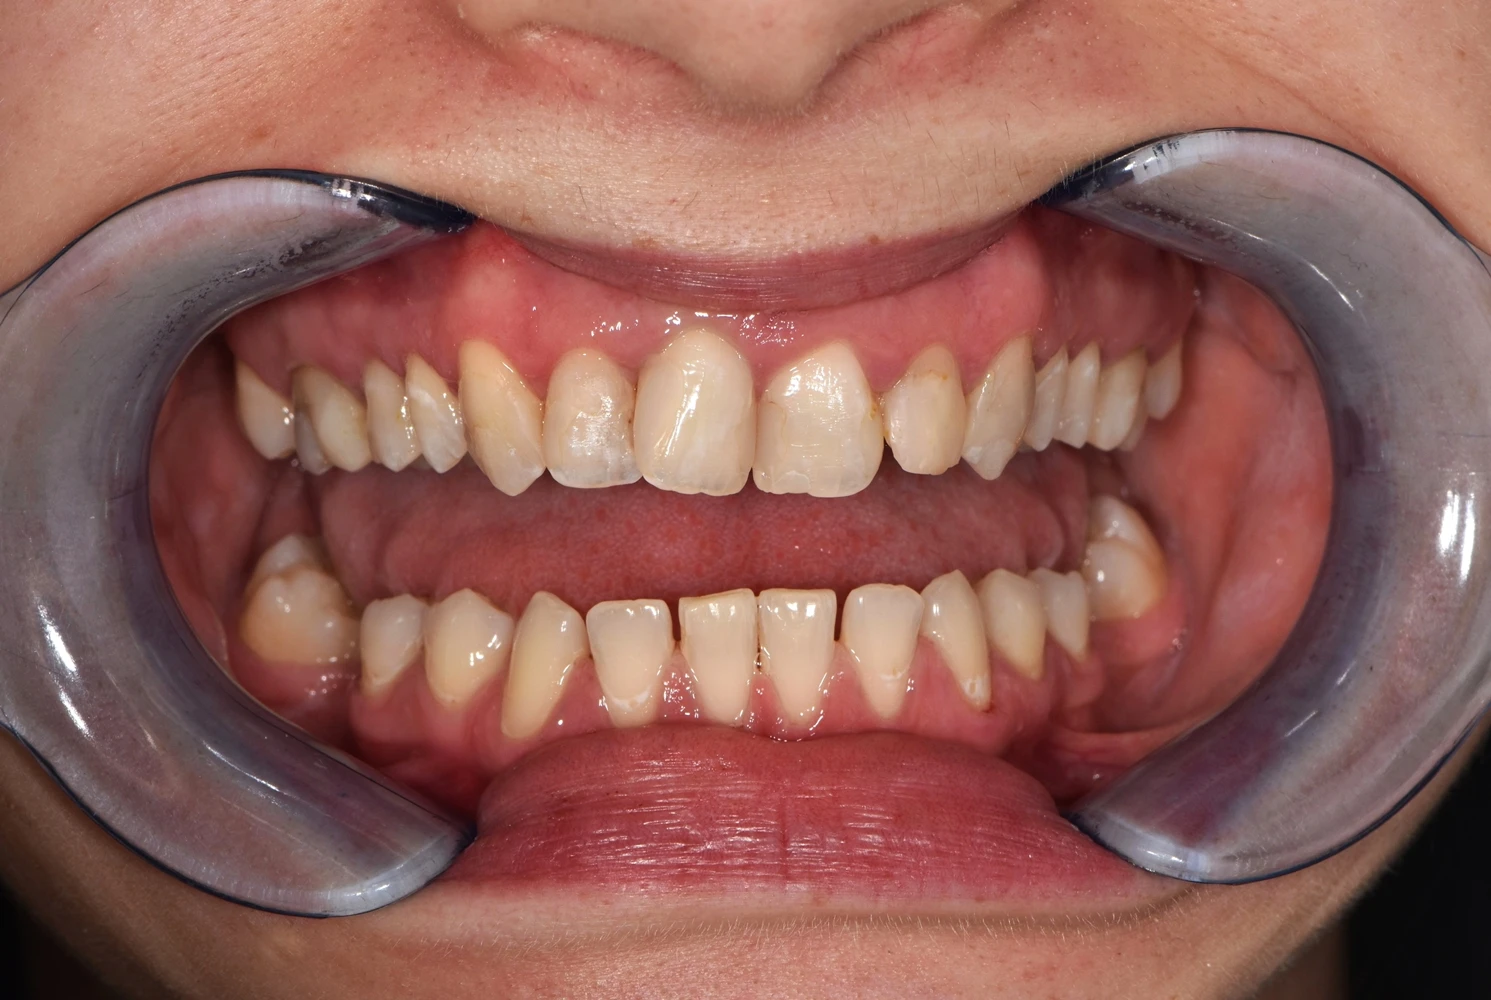

Caz de reabilitare totală orală.

Provocarea acestui caz a fost in reabilitarea totală a pacientului atâta a maxilarului superior cat și a mandibulei, tratând absolut toți dinții prezenți și reconstruindu-i cu pivoți de fibră de sticlă pentru a putea obține o susținere suficientă pentru viitoarele coroane.

Grupul superior fiind distrus complet, am efectuat tratamente la microscop, reconstrucția individuală a fiecărui dinte, tratamente parodontale cu laser pentru sănătatea ginigivala și am optat pentru coroane individuale de zirconiu ceramică pentru un plus de duritate și protecție a dinților cat și pentru o estetică frumoasă. Au fost folosite un set de provizorii de lungă durată pentru reechilibrarea articulației și muscaturii.

Pacientul a beneficiat inferior de igienizare în profunzime , detartraj și airflow, tratamente endodontice , obturații ( plombe) , tratamente parodontale cu laser iar în final punți și coroane individuale de zirconiu ceramica.

Termen de finalizare 2 săptămîni de la amprentarea finală.